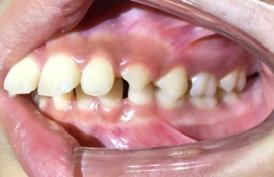

❶ 个别前牙反牙合:此类错牙合可使下颌前伸运动受限。

前

后

❷ 前牙反牙合:此类错牙合影响下颌前伸,影响上颌发育。